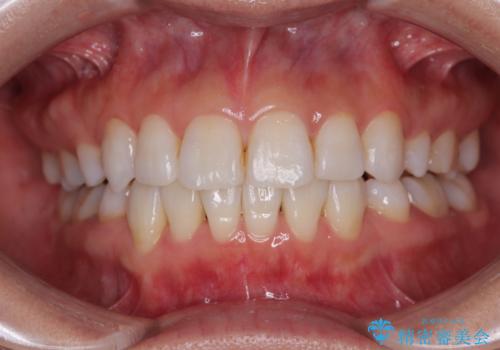

- 上下前歯の後戻りを気にして来院された患者様です。

インビザラインでの治療を希望されていて、デコボコの程度が中等度であり、安価なパッケージにて対応可能と判断されたため、インビザライン・モデレートを用いて矯正治療を行うこととしました。

インビザライン・モデレートは、製作できるアライナーの枚数に制限があるため、移動可能な量に限りがあるものの、インビザライン・ライトよりも枚数が多いため、幅広い症例に対応可能です。